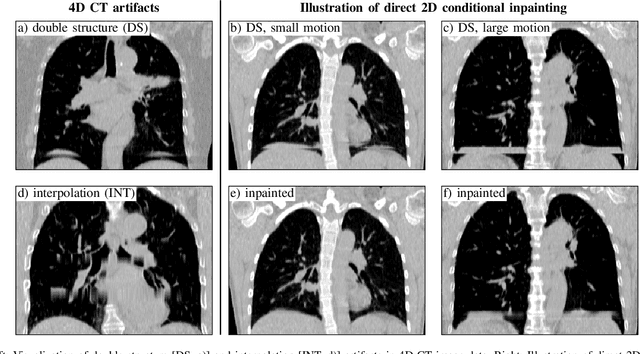

Abstract:4D CT imaging is an essential component of radiotherapy of thoracic/abdominal tumors. 4D CT images are, however, often affected by artifacts that compromise treatment planning quality. In this work, deep learning (DL)-based conditional inpainting is proposed to restore anatomically correct image information of artifact-affected areas. The restoration approach consists of a two-stage process: DL-based detection of common interpolation (INT) and double structure (DS) artifacts, followed by conditional inpainting applied to the artifact areas. In this context, conditional refers to a guidance of the inpainting process by patient-specific image data to ensure anatomically reliable results. Evaluation is based on 65 in-house 4D CT data sets of lung cancer patients (48 with only slight artifacts, 17 with pronounced artifacts) and the publicly available DIRLab 4D CT data (independent external test set). Automated artifact detection revealed a ROC-AUC of 0.99 for INT and 0.97 for DS artifacts (in-house data). The proposed inpainting method decreased the average root mean squared error (RMSE) by 60% (DS) and 42% (INT) for the in-house evaluation data (simulated artifacts for the slight artifact data; original data were considered as ground truth for RMSE computation). For the external DIR-Lab data, the RMSE decreased by 65% and 36%, respectively. Applied to the pronounced artifact data group, on average 68% of the detectable artifacts were removed. The results highlight the potential of DL-based inpainting for the restoration of artifact-affected 4D CT data. Improved performance of conditional inpainting (compared to standard inpainting) illustrates the benefits of exploiting patient-specific prior knowledge.